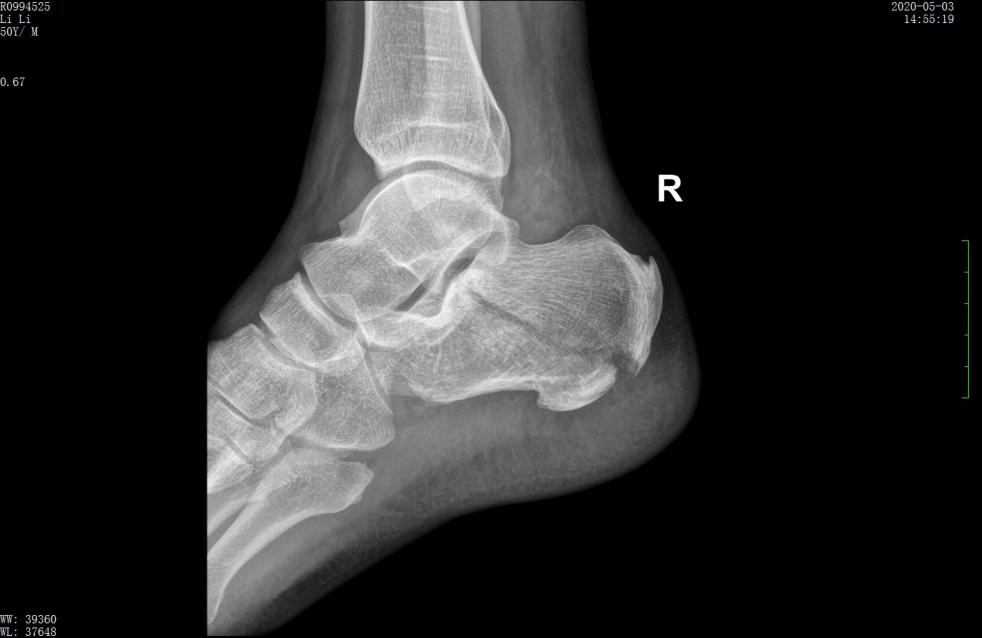

L形外侧切口 | 术前

术前X线示跟骨高度丢失,关节面塌陷

术前X线示骨折分离移位